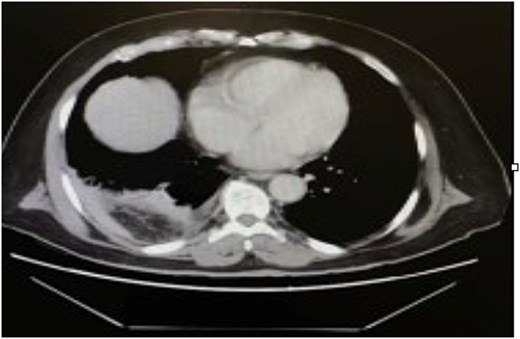

The patient was initially resuscitated with intravenous fluids. An urgent abdominal computed tomography (CT) scan was performed, revealing a herniated and obstructed segment of large bowel loops with mesenteric fat at the hepatic flexure, likely through the posterior right hemidiaphragm (Fig. 1). The scan showed a proximally dilated cecum and ascending colon, with a transitional zone observed at the neck of the hernia, leading to a distally collapsed colon. Additionally, there was an area suspicious for pneumatosis intestinalis within the obstructed bowel segment, along with adjacent fat stranding and free fluid—findings that raised concerns for strangulation or early ischemia. The scan also indicated a right-sided pleural effusion and adjacent atelectasis (Fig. 2).

CT scan of the abdomen revealed a herniated obstructed segment of large bowel loops and mesenteric fat at the hepatic flexure, likely through the posterior right hemidiaphragm.